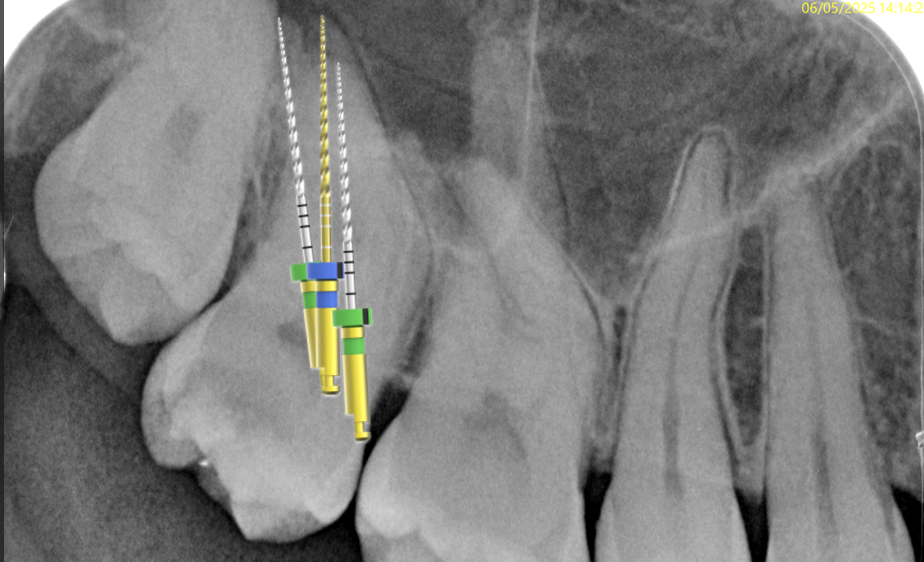

Fig. 6

Then I used the R1 file (13/.03) short to the estimated working length

Fig. 7

After that, I kept pre-flaring the root canals using the R2 (25/.04)